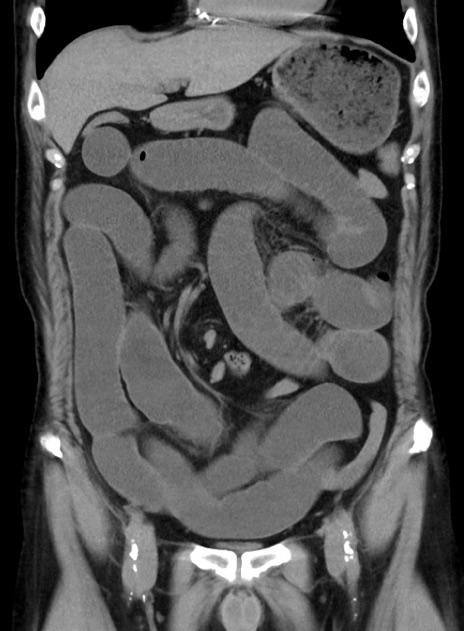

症例38(冠状断像)

【症例】70歳代 男性

【主訴】腹痛・嘔吐

【現病歴】昨晩より、嘔吐・腹痛あり。今朝になっても嘔吐あり。来院。

【既往歴】心臓バイパス手術、開腹胆摘、腸閉塞

【身体所見】BP 107/71mmHg、HR 116/min、腹部:平坦、軟、下腹部に軽度圧痛あり。反跳痛なし。

【データ】WBC 15100、CRP 0.32